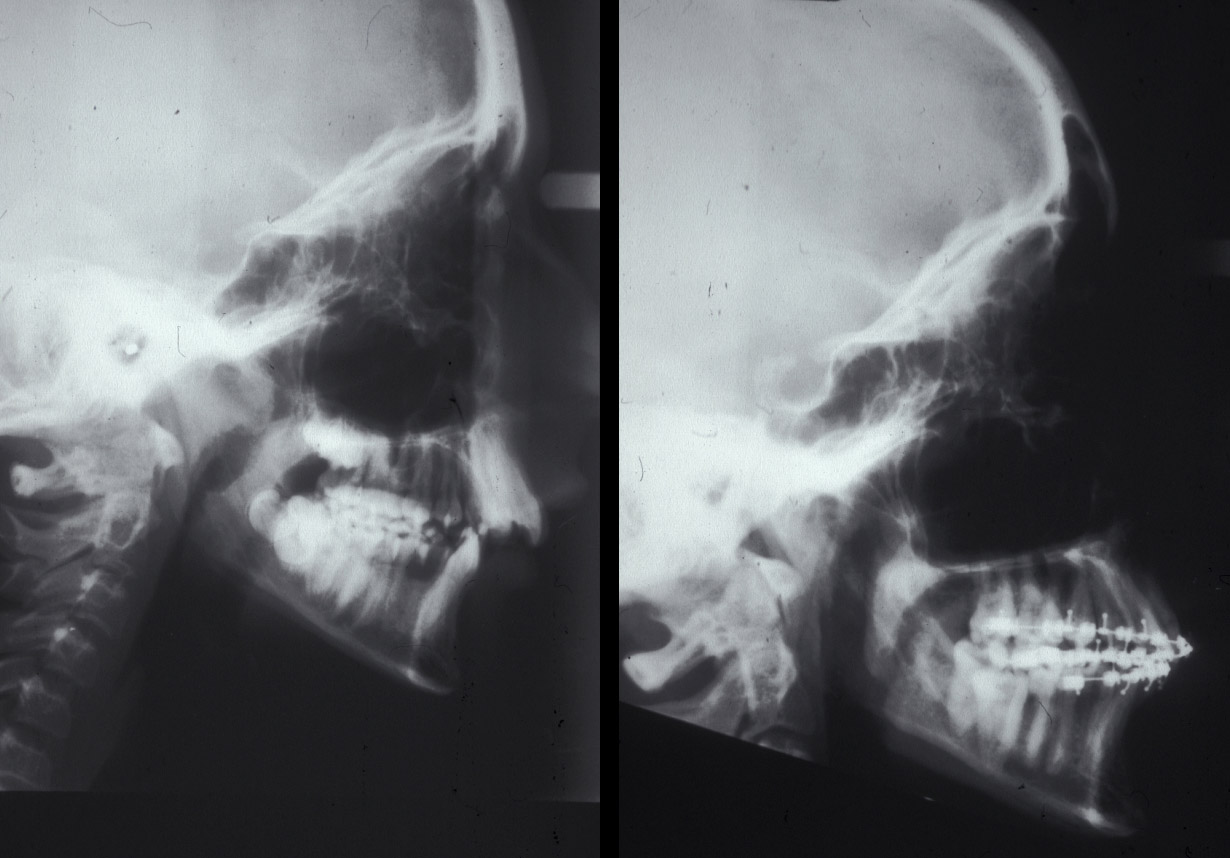

A lateral cephalogram (a profile side-view X-ray image of the skull and soft tissues) is required. This view supplements clinical analysis with cephalometric analysis (a range of measurements of the head and skull). See Figure 9 for an example of a lateral cephalogram.

Figure 9: A lateral cephalogram of a patient with a class III malocclusion.

Figure 17: Lateral cephalograms of a case of class II malocclusion before (left) and during (right) orthodontic decompensation.